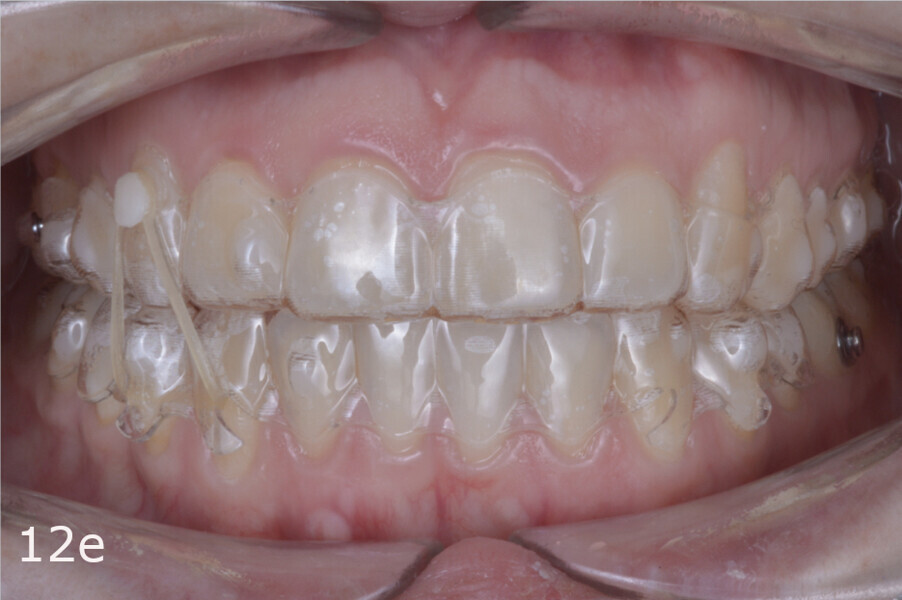

The treatment objectives included closing the anterior open bite, achieving a bilateral Angle Class I relationship and a proper overjet and overbite, correcting the midline discrepancies, and achieving a profile harmonisation. The treatment plan consisted of orthodontic camouflage treatment with asymmetric distalisation in three of the four quadrants using Invisalign aligners (Align Technology) and third molar extraction. The Invisalign Comprehensive package was chosen, and 63 pairs of aligners were used (Figs. 7–10). Each aligner was worn for 20 hours a day for one week each. The use of Class III elastics on both sides was indicated. Afterwards, ten refinement aligners were needed to improve the interdigitation on the right side (Figs. 11 & 12).